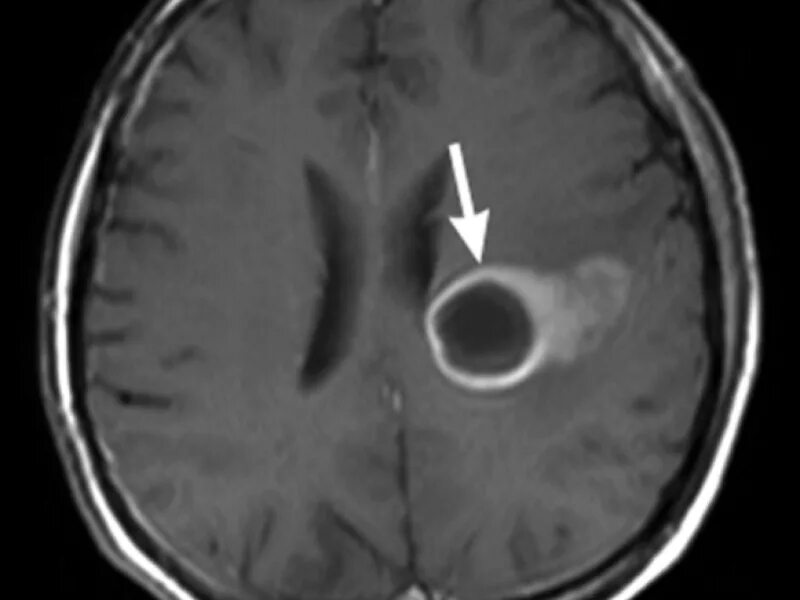

Перифокальный отек образования